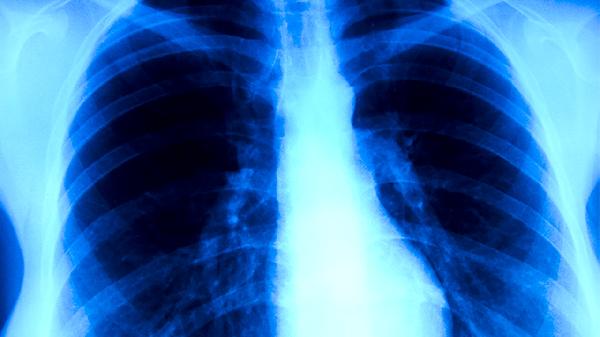

典型肺结核的基本症状主要有咳嗽、咳痰、咯血、胸痛、发热等。肺结核是由结核分枝杆菌感染引起的慢性传染病,主要侵犯肺部,也可累及其他器官。

肺结核患者早期常出现持续性干咳,随着病情进展可转为咳痰。咳嗽多持续2周以上,晨起或夜间加重。这种症状与结核分枝杆菌刺激支气管黏膜有关。若出现长期不愈的咳嗽,建议及时就医进行痰涂片检查或胸部影像学检查。

肺结核患者咳出的痰液多为白色黏液痰,病情加重时可变为黄绿色脓性痰。部分患者痰中可带血丝。痰液检查是诊断肺结核的重要依据,可发现结核分枝杆菌。患者应注意将痰液吐入专用容器,避免传播病菌。

约三分之一的肺结核患者会出现咯血症状,表现为痰中带血或大量咯血。这是由于结核病变侵蚀肺部血管所致。少量咯血可使用云南白药胶囊等止血药物,大量咯血需立即就医,可能需使用垂体后叶素注射液等药物止血。

肺结核引起的胸痛多为钝痛或隐痛,咳嗽或深呼吸时加重。胸痛可能与胸膜受累或肺部炎症刺激有关。可遵医嘱使用布洛芬缓释胶囊缓解疼痛,但需注意止痛药不能替代抗结核治疗。

肺结核患者常出现午后低热,体温多在37.5-38.5℃之间,伴有盗汗、乏力等症状。这种发热与结核分枝杆菌释放的毒素和机体免疫反应有关。确诊后需规范使用异烟肼片、利福平胶囊等抗结核药物,不可自行使用退热药掩盖症状。